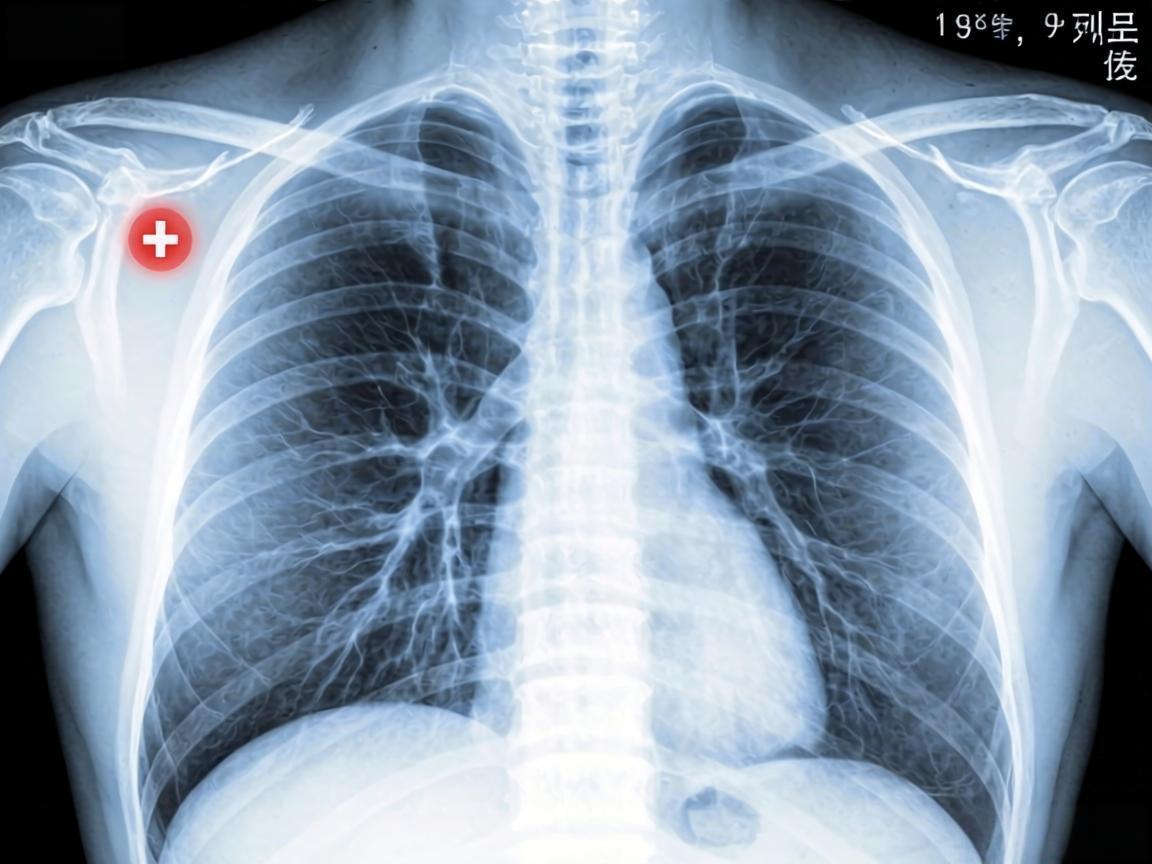

肺部阴影是否需要手术?

患者发现左肺上叶2.0cm片状影,医生建议手术,家属犹豫不决,特来咨询。已定期复查CT,无明显进展,暂无需用药,主张戒烟限酒、密切随访观察。

从5大癌症体检清单做对检查关键时刻能救命。肺癌选低剂量螺旋CT;结直肠癌首选肠镜;乳腺癌推荐彩超+钼靶;肝癌需每半年做肝脏彩超+甲胎蛋白;宫颈癌必查HPV+TCT联合筛查。普通体检≠防癌筛查,专项检查不能少。